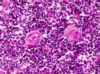

מהם תאי פלסמה?

תאים מסוג לימפוציטים B

במצב של שיא השפעול- בהירים, הרבה ציטופלזמה (לעומת תאים במצב שאינו השפעול)